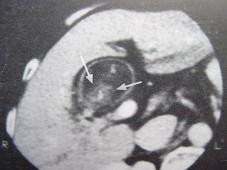

问题 男,55岁,上腹部隐痛1月余,CT检查如图,最可能的诊断是()

选项 A.胆囊结石 B.胆囊癌(腔内型) C.胆囊腺肌增生症 D.胆囊息肉 E.胆囊转移瘤

答案 B